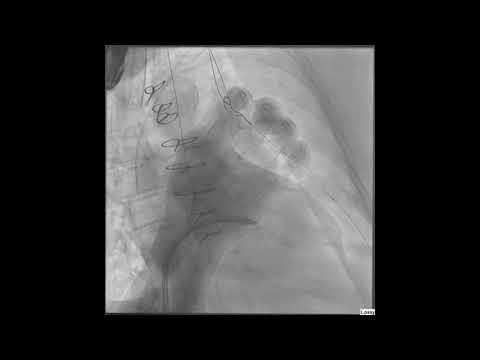

LIVE CASE 3 SAPIEN 3 TAVR with Difficult Vascular Access